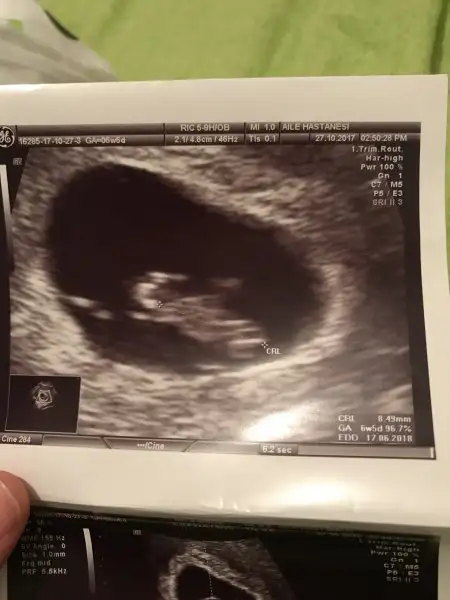

Canım keseye göre erkek gibi sağa daha yatkın.Rabbim gönlüne göre versin ınş.

Canım cok tesekkür ederim. Saglıklı olsundaCanım keseye göre erkek gibi sağa daha yatkın.Rabbim gönlüne göre versin ınş.

Masallah ne kadar guzel ya ikiz olmasi birisi daha uzun biri yuvarlak ya bence ona fore uzuna erkek digerine kiz dediler gonlunuzden gecen olsun insBenimkilerede bi baksanız annem biri kızbiri erkek dedi

Bende biri kız biri erkek diyorum sağlıkla gelsinler ınş.Benimkilerede bi baksanız annem biri kızbiri erkek dedi